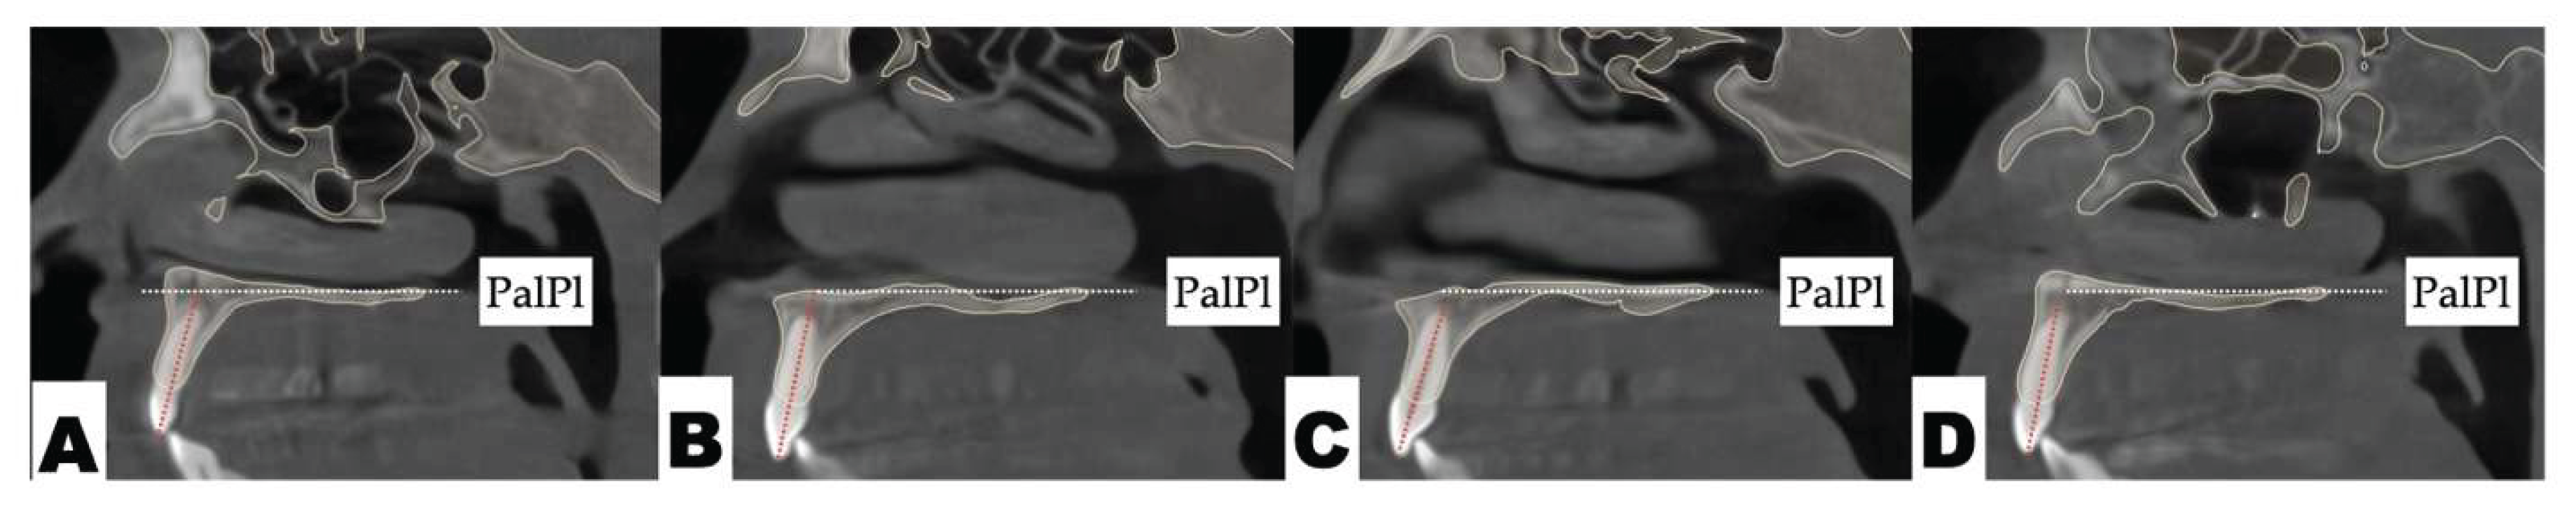

Background: While mini-screw-assisted rapid palatal expansion (MARPE) is effective for correcting maxillary transverse deficiency in adults, perimaxillary suture disarticulation—particularly at the pterygomaxillary junction—can be inconsistent. This study evaluates skeletal and dentoalveolar outcomes of a novel 3D-guided midpalatal piezocorticotomy-assisted MARPE protocol, focusing on expansion symmetry and pre-existing asymmetries. Methods: Three adult patients were retrospectively analyzed after treatment with 3D-guided midpalatal piezocorticotomy-assisted MARPE expansion and one with non-guided midpapalatal piezocorticotomy and MARPE expansion. Surgical guides were digitally designed using CBCT data to align with the nasal septum orientation in multiple planes. Perimaxillary suture disarticulation was measured pre- and post-expansion, and dentoalveolar changes were evaluated. Post-expansion asymmetries were addressed using directly printed aligners. Results: Complete midpalatal suture separation (mean 8.48 mm), involving both anterior and posterior nasal spine regions, was achieved in one patient. Bilateral pterygomaxillary disarticulation averaged 1.06–1.23 mm, resulting in forward–outward rotation of the nasomaxillary complex. Additional separation occurred at the frontonasal (2.03 mm) and vomeromaxillary (1–2 mm) sutures, with no significant changes in orbital or peri-orbital sutures. One patient presented with pre-existing dentoalveolar asymmetry, which intensified the perceived post-expansion imbalance but was successfully corrected with directly printed aligners. In the second case, 5.6 mm of suture separation resulted in a limited lateral nasal width increase (<1.5 mm), while maxillary base expansion exceeded 6 mm. A significant canine plane cant (1.2 mm) and divergent axial inclinations of the maxillary central incisors relative to the palatal plane were also observed. In the second case, a non-impactful palatal bone fracture with asymmetric displacement of the left palatine fragment was documented. After 16 months of aligner therapy, all cases exhibited favorable remodeling of the palatal structures, midpalatal suture, and alveolar processes, accompanied by improved dental alignment, occlusal plane symmetry, and mandibular dentoalveolar adaptation. The dento-alveolar expansion achieved in the third case over the course of 16 months of treatment was approximated at 4 mm. The fourth case showed consistent improvement with direct printed aligners after MARPE midpalatal diasrticulation of 11 mm after experiencing minor bone fracture. Conclusions: Human skulls exhibit considerable variability between the left and right sides, which can influence spatial balance. Pre-existing cranial asymmetries appear to be the primary contributors to asymmetry following MARPE treatment. Careful evaluation of dentoalveolar discrepancies and axial tooth inclinations is essential for preventing and managing potential asymmetric dental arch outcomes during the post-expansion phase. Although peri-maxillary bone fractures are relatively uncommon, their occurrence is influenced by multiple factors. Adjunctive techniques, such as 3D-guided midpalatal piezocorticotomy, show promise in significantly lowering the risk of intra-expansion peri-maxillary fractures.